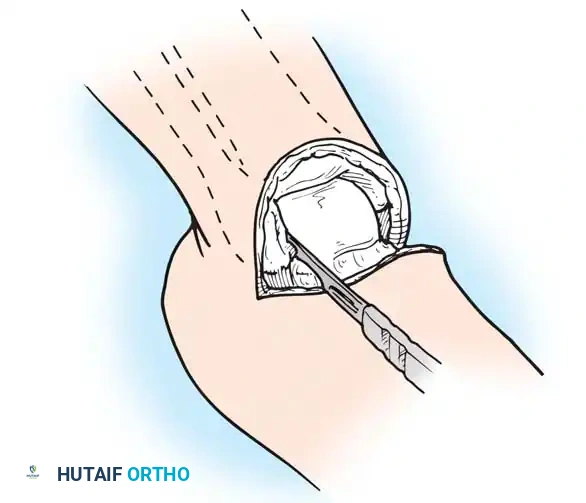

Step 3: Posterior Dissection and Calcanectomy

- Place a bone hook into the posterior aspect of the talus to provide forceful equinus traction. Proceed with posterior dissection, dividing the posterior capsule of the ankle joint.

- Identify the Achilles tendon. Divide it directly at its insertion on the calcaneus.

Pitfall: Do not damage the overlying posterior skin during Achilles tenotomy. Buttonholing the skin here will lead to necrosis of the entire heel flap.

- Using a periosteal elevator, dissect the soft tissues from the lateral and medial surfaces of the calcaneus. Pull the bone into extreme equinus.

- Continue subperiosteal dissection on the inferior surface of the calcaneus until the distal end of the plantar skin flap is reached. Remove the entire foot, leaving only the heel flap.